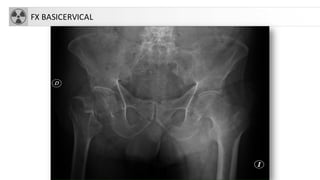

CLASIFICACIÓN

• Fracturascapitales: raras, asociadas a

luxación

• Fracturascervicales (intraarticulares)

1. subcapitales.

2. transcervicales

3. basicervicales

• 4. Fracturastrocantereas:

• cervicotrocantereas

• pertrocantereas(+frecuente)

• 5. Fracturassubtrocantereas

• Aisladas de trocanter mayor

• Aisladas de trocánter menor

FX BASICERVICAL